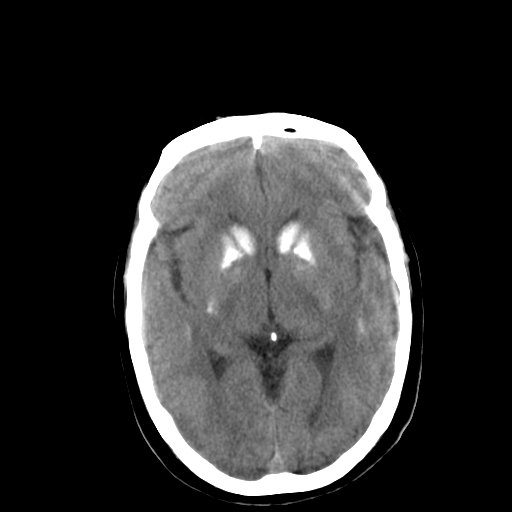

标题: CT13482:对称钙化!外伤就诊!

女,58 ,对称钙化!外伤就诊!